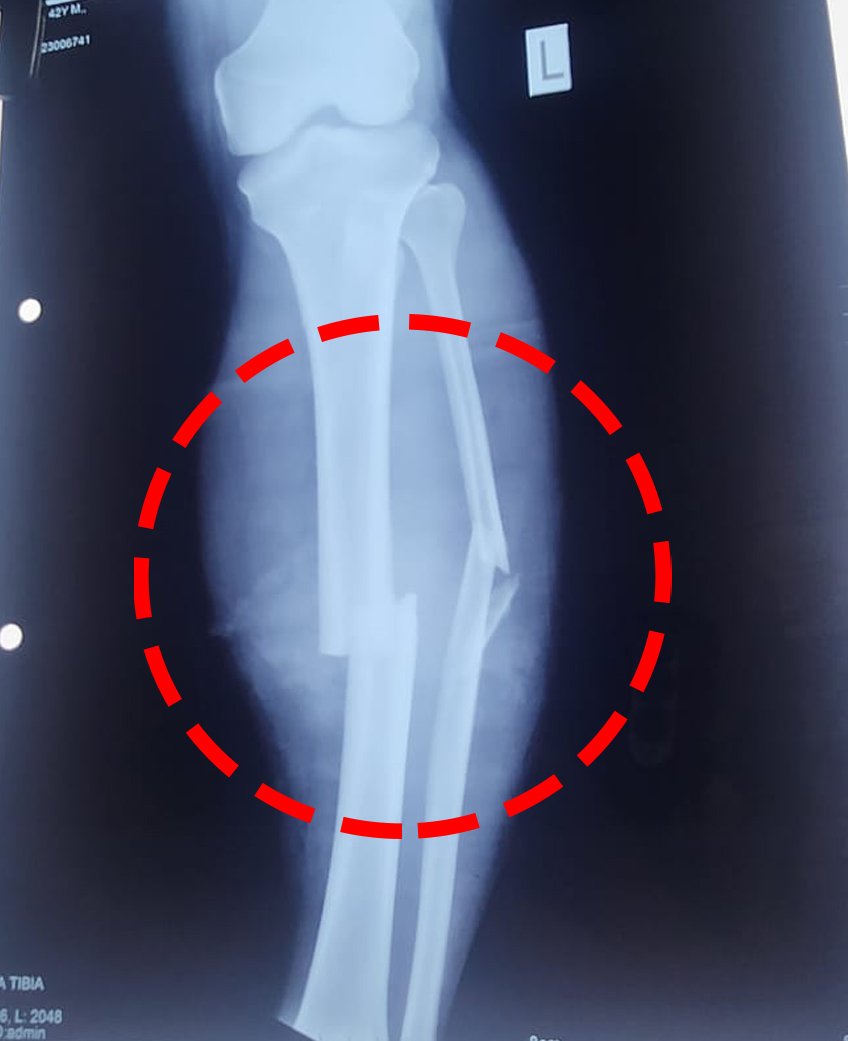

सभी के हाथों में हथौड़े, लोहे की रॉड़, सरिया, बर्फ तोड़ने वाला सुआ, देसी कट्टे थे । विजय ने बताया कि सभी टोल पर आते ही सीधे विजय के कैबिन में आ गए और आते ही विजय पर हथियारों से हमला कर दिया । गुंडों ने हथौड़े और लोहे की रॉड, सरिए से विजय के हाथ पैर तोड़ दिए और पेट में सुए से हमला कर दिया । सभी 9-10 आरोपी विजय को अधमरा करके मौके से फरार हो गए ।